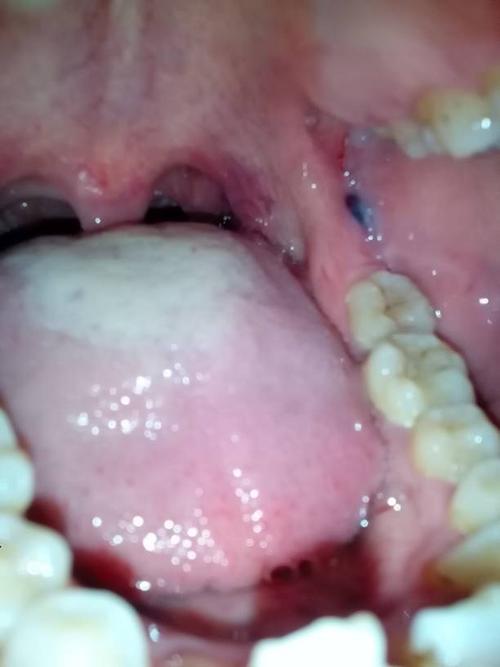

牙龈出血是常见的口腔疾病,一般情况下,只要及时治疗,就能得到缓解。

但是,如果牙龈出血量比较大,而且持续时间比较长,就要引引起注意了,这可能是身体发出的求救信号。因为牙龈出血的原因有很多,比如牙周炎、牙龈肿痛等,都会导致牙龈出血。所以,当牙龈出血时,不为是小事,一定要及时就医检查,避免病情恶化。

正常情况下,我们每天都会刷牙,但是有些人刷牙时会感觉牙龈出血,这是因为牙龈受到细菌的侵蚀,导致牙牙龈发炎,从而引起牙龈出血。如果经常出现这种情况,一定要及时去医院检查,避免病情加重。